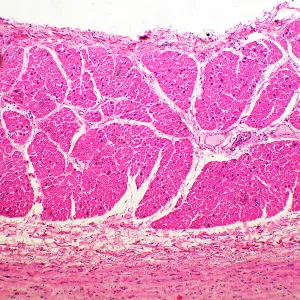

Микроскоп MAGUS Bio 260T – рутинный, с ним можно проводить лабораторные и научные исследования, или использовать его для учебного процесса. Микроскоп работает с тонкими прозрачными и полупрозрачными препаратами в светлом поле. Однако на прибор можно поставить дополнительные компоненты, которые расширят его возможности для проведения исследований по методам темного поля, фазового контраста, в поляризованном и люминесцентном свете.

Дополнительные элементы расширят функционал прибора. Набор окуляров увеличит спектр увеличения. Для дополнительных методов работы с препаратами, которые невозможно рассмотреть в светлом поле, нужно дополнить микроскоп фазово-контрастным устройством, слайдером темного поля или устройством простой поляризации. Цифровая камера поможет зафиксировать на фото или видео результаты исследования или выведет картинку на экран. Измерить объекты можно, применяя калибровочный слайд вместе с окуляром со шкалой или с цифровой камерой.